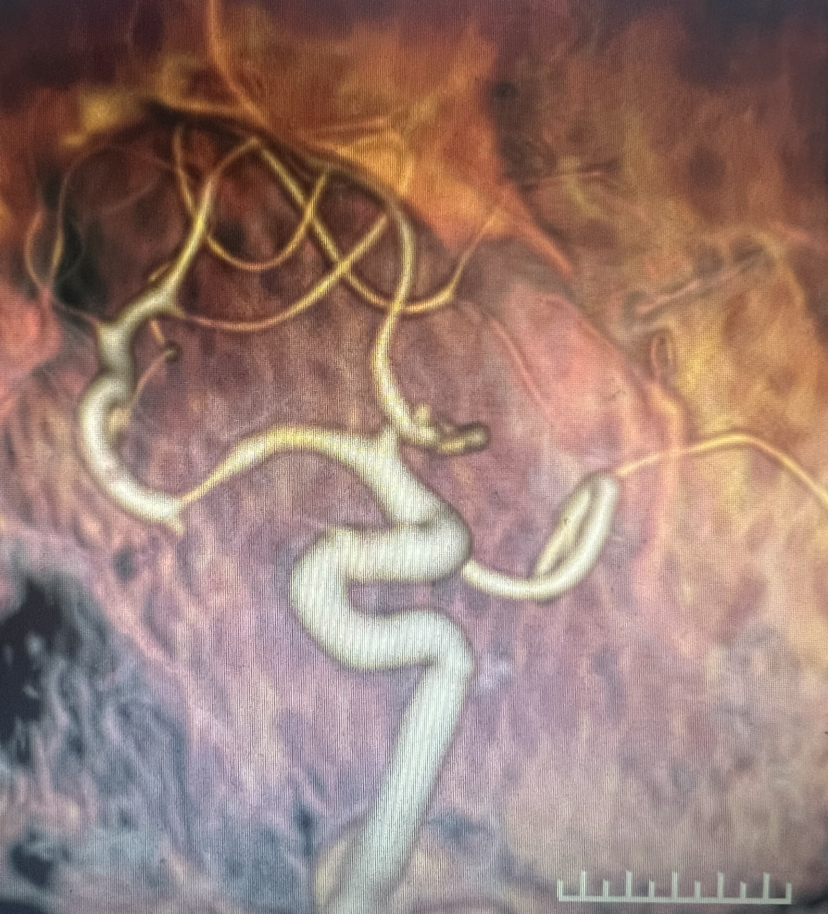

4、急诊CTA:

DSA:双侧大脑前动脉A1段存在,右侧A1段与前交通动脉结合处囊状凸起,最大径约2.8m m